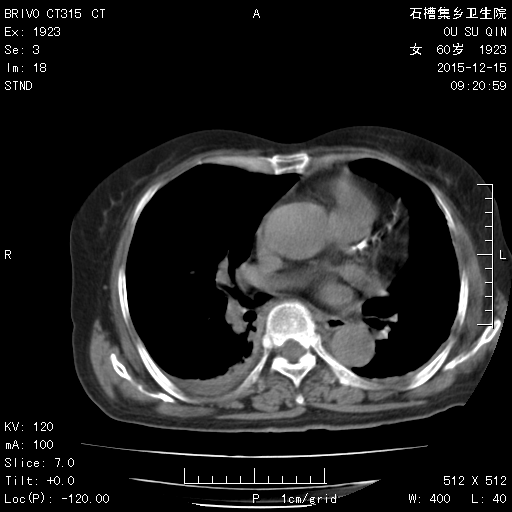

CT51427:患者 f 60Y 发热 腹痛三天

本帖最后由 cefcmj 于 2015-12-15 18:12 编辑 右侧胸腔积液, 急性胆囊炎? 请老师们指点?

急性化脓性胆囊炎,腹水,双侧胸腔少量积液

急性胆囊炎,腹水,双侧胸腔积液。